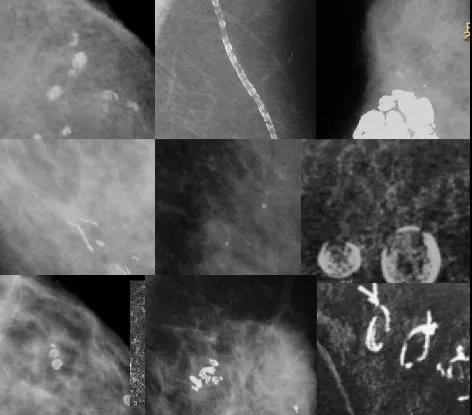

(二) 钙化:

良性钙化常比恶性钙化大,呈较粗糙的钙化或边缘清晰的圆形钙化。恶性钙化常较小,需要放大来帮助显示。

对钙化的描述从形态和分布两方面进行。良性钙化可不描写,但当这些钙化可能会引起另外医生误解时,这些良性钙化需要描述。

1、形态:分为典型良性钙化、中间性钙化(可疑钙化) 、高度恶性可能的钙化三种。

1.1 典型良性钙化有以下10 种典型表现:

① 皮肤钙化较粗大,典型者中心呈透亮改变,不典型者可借助切线投照予以鉴别;

② 血管钙化表现为管状或轨道状;

③ 粗糙或爆米花样钙化直径常大于2 - 3 mm , 为纤维腺瘤钙化的特征表现;

④ 粗棒状钙化连续呈棒杆状,偶可分支状, 直径通常大于1 mm ,可能呈中央透亮改变,边缘光整,沿着导管分布,聚向乳头,常为双侧乳腺分布,多见于分泌性病变;

⑤ 圆形和点状钙化,小于1 mm甚至0. 5 mm,常位于小叶腺泡中,簇状分布者要引起警惕;

⑥ “环形”或“蛋壳样钙化”,环壁很薄,常小于1 mm ,为球形物表面沉积的钙化,见于脂肪坏死或囊肿;

⑦ 中空状钙化大小可从1 mm 到1 cm 甚至更大,边缘光滑呈圆形或卵圆形,中央为低密度,壁的厚度大于“环形”或“蛋壳样”钙化,常见于脂肪坏死、导管内钙化的残骸,偶可见于纤维腺瘤;

⑧ 牛奶样钙化为囊肿内钙化,在头足轴位(CC)表现不明显,为绒毛状或不定形状, 在90°侧位上边界明确,根据囊肿形态的不同而表现为半月形、新月形、曲线形或线形,形态随体位发生变化是这类钙化的特点;

⑨ 缝线钙化是由于钙质沉积在缝线材料上所致,尤其在放疗后常见,典型者为线形或管形,绳结样改变常可见到。

⑩ 营养不良性钙化常在放疗后或外伤后的乳腺上见到,钙化形态不规则,多大于0. 5 mm,呈中空状改变。

1.2 中间性钙化(可疑钙化):包括不定型模糊钙化和粗糙不均质钙化两种。

① 不定型模糊钙化:形态上常小而模糊无典型特征,弥漫性分布常为良性表现,而簇状分布、区域性分布、线样和段样分布需提请临床活检。

② 粗糙不均质钙化:多大于0. 5 mm , 形态不规则可能为恶性改变,也可出现在良性的纤维化、纤维腺瘤和外伤后的乳腺中,需结合分布情况考虑。

1.3高度恶性可能的钙化也有两种表现形式,细小的多形性钙化(颗粒点状钙化)和线样或线样分支状钙化(铸形钙化)。

① 颗粒点状钙化较不定形钙化更可疑, 大小形态不一, 直径常小于0. 5 mm。

② 线样分支状钙化表现为细而不规则的线样,常不连续,直径小于0. 5 mm ,这些征象提示钙化是从被乳腺癌侵犯的导管腔内形成的。

高度恶性可能钙化的特征就是不均质性,包括形态、大小和密度。